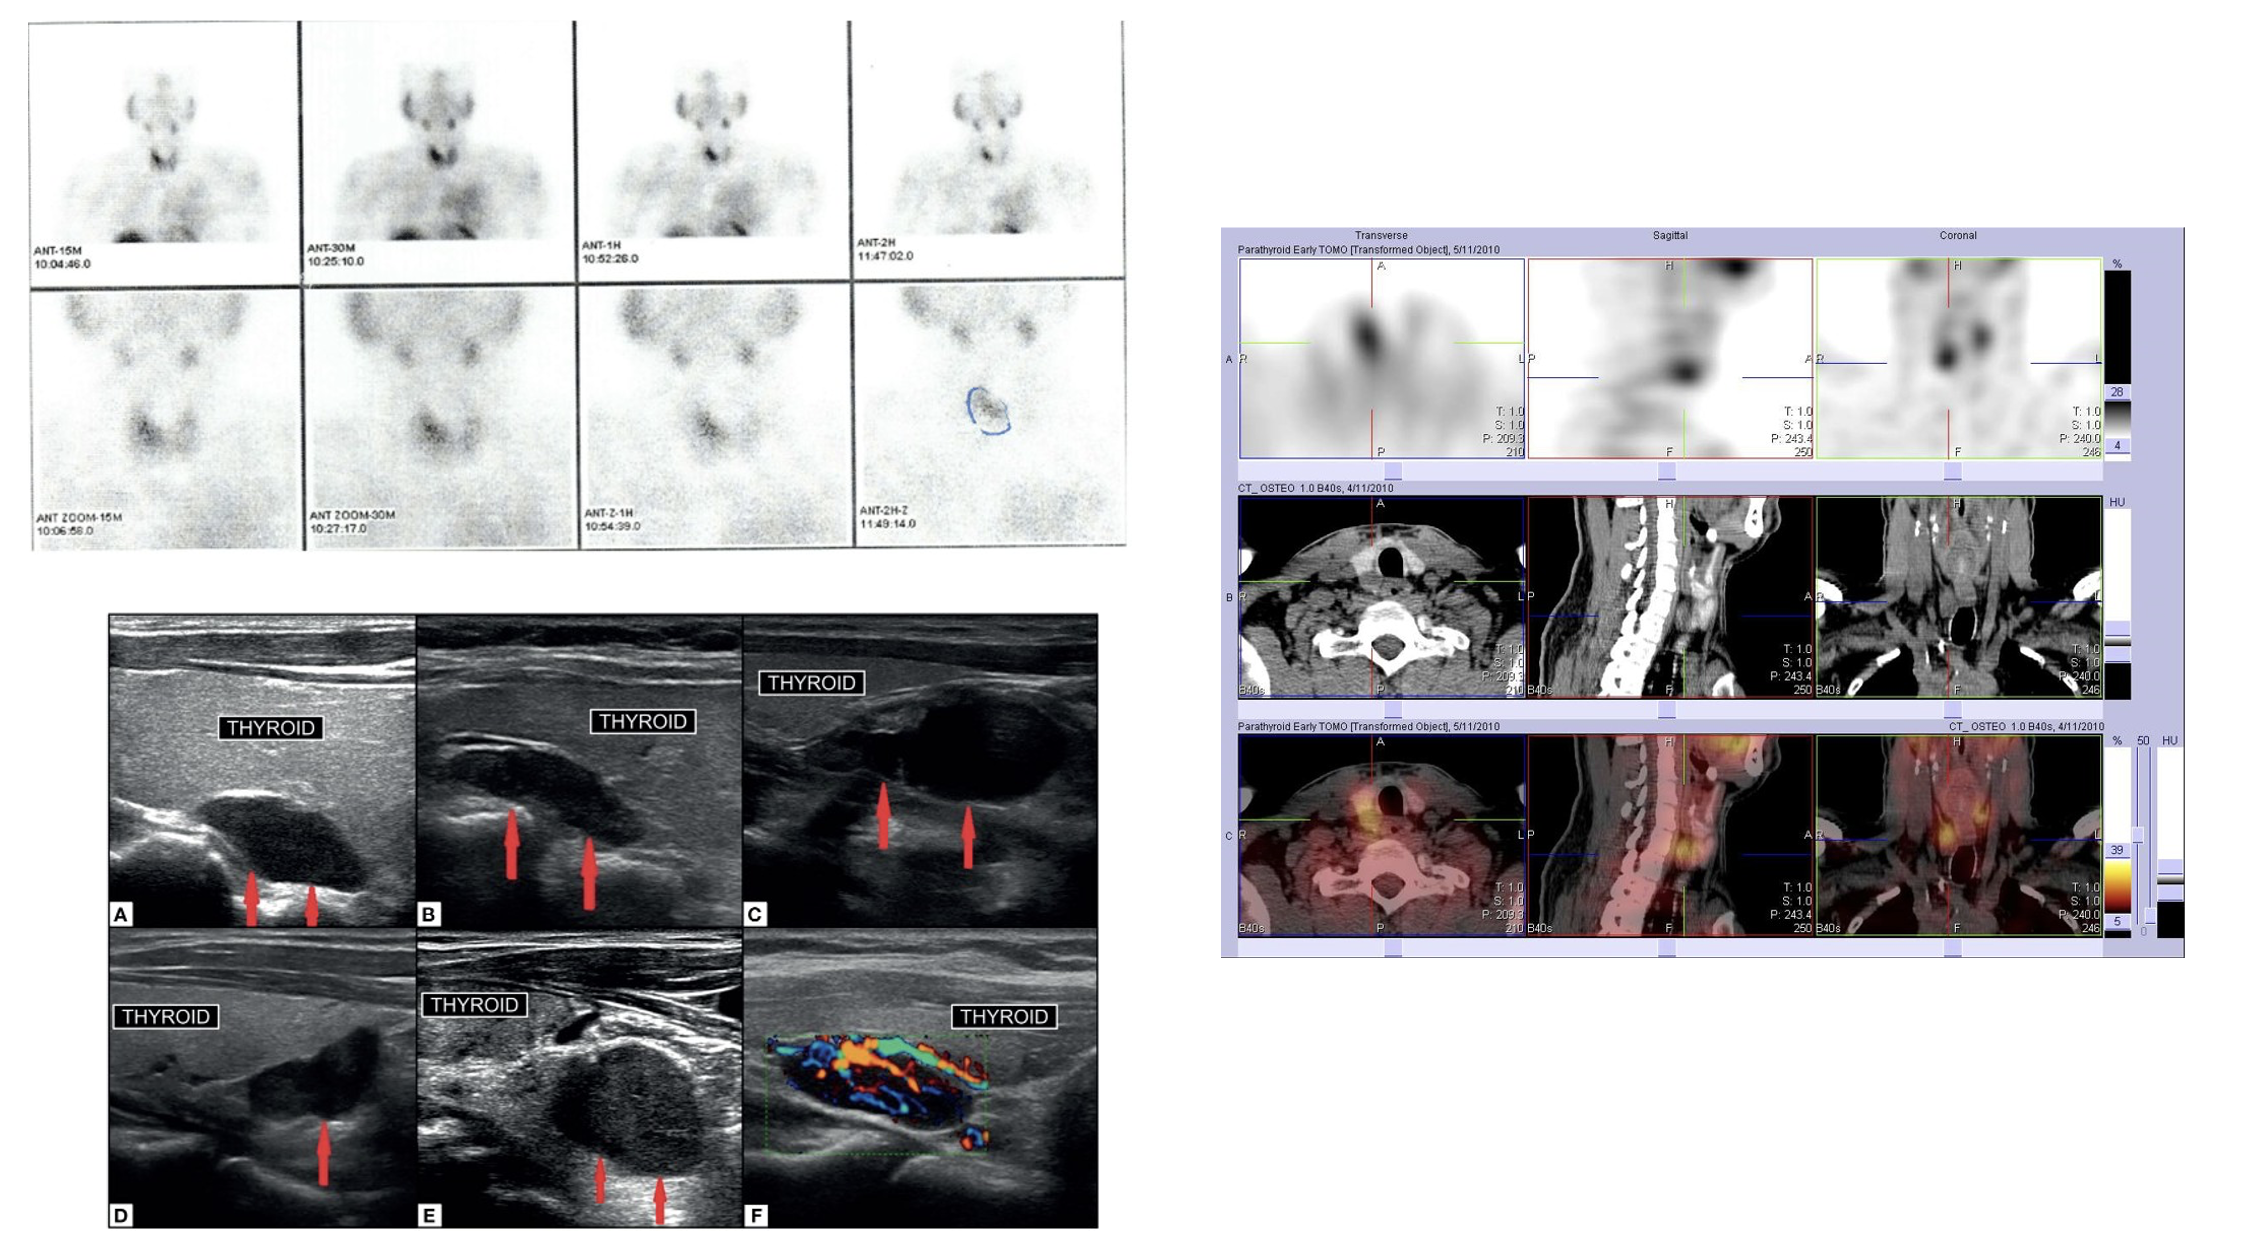

1. 副甲狀腺掃描(Parathyroid scan)

• 放射性同位素鎝製劑 (Tc-99m MIBI) 核子掃描 配合 單光子放射電腦雙融掃描 (SPECT/CT)

• Tc-99m MIBI scan: 透過靜脈注射一種放射性同位素鎝製劑,它會被副甲狀腺細胞吸收。 但聚集速度在正常和異常副甲狀腺組織中有所不同。如果副甲狀腺有病變(如腺瘤),它會吸收更多的藥物,並在影像中顯示出來,而正常或未病變的副甲狀腺則吸收較少。在注射後的一段時間內,會進行數次掃描,來判斷病理位置。

• SPECT/CT: 是一個整合性影像結合了功能與結構影像,可同時提供病理的解剖位置和功能及代謝狀態,再進一步提高診斷的精確度。

2. 頸部超聲波檢查 (ultrasound neck)

• 超聲波檢查是一種無輻射、操作簡便的影像技術,能幫助評估腫瘤的大小、位置、形狀和數量。也可以在手術中協助定位及找出腫瘤的位置。